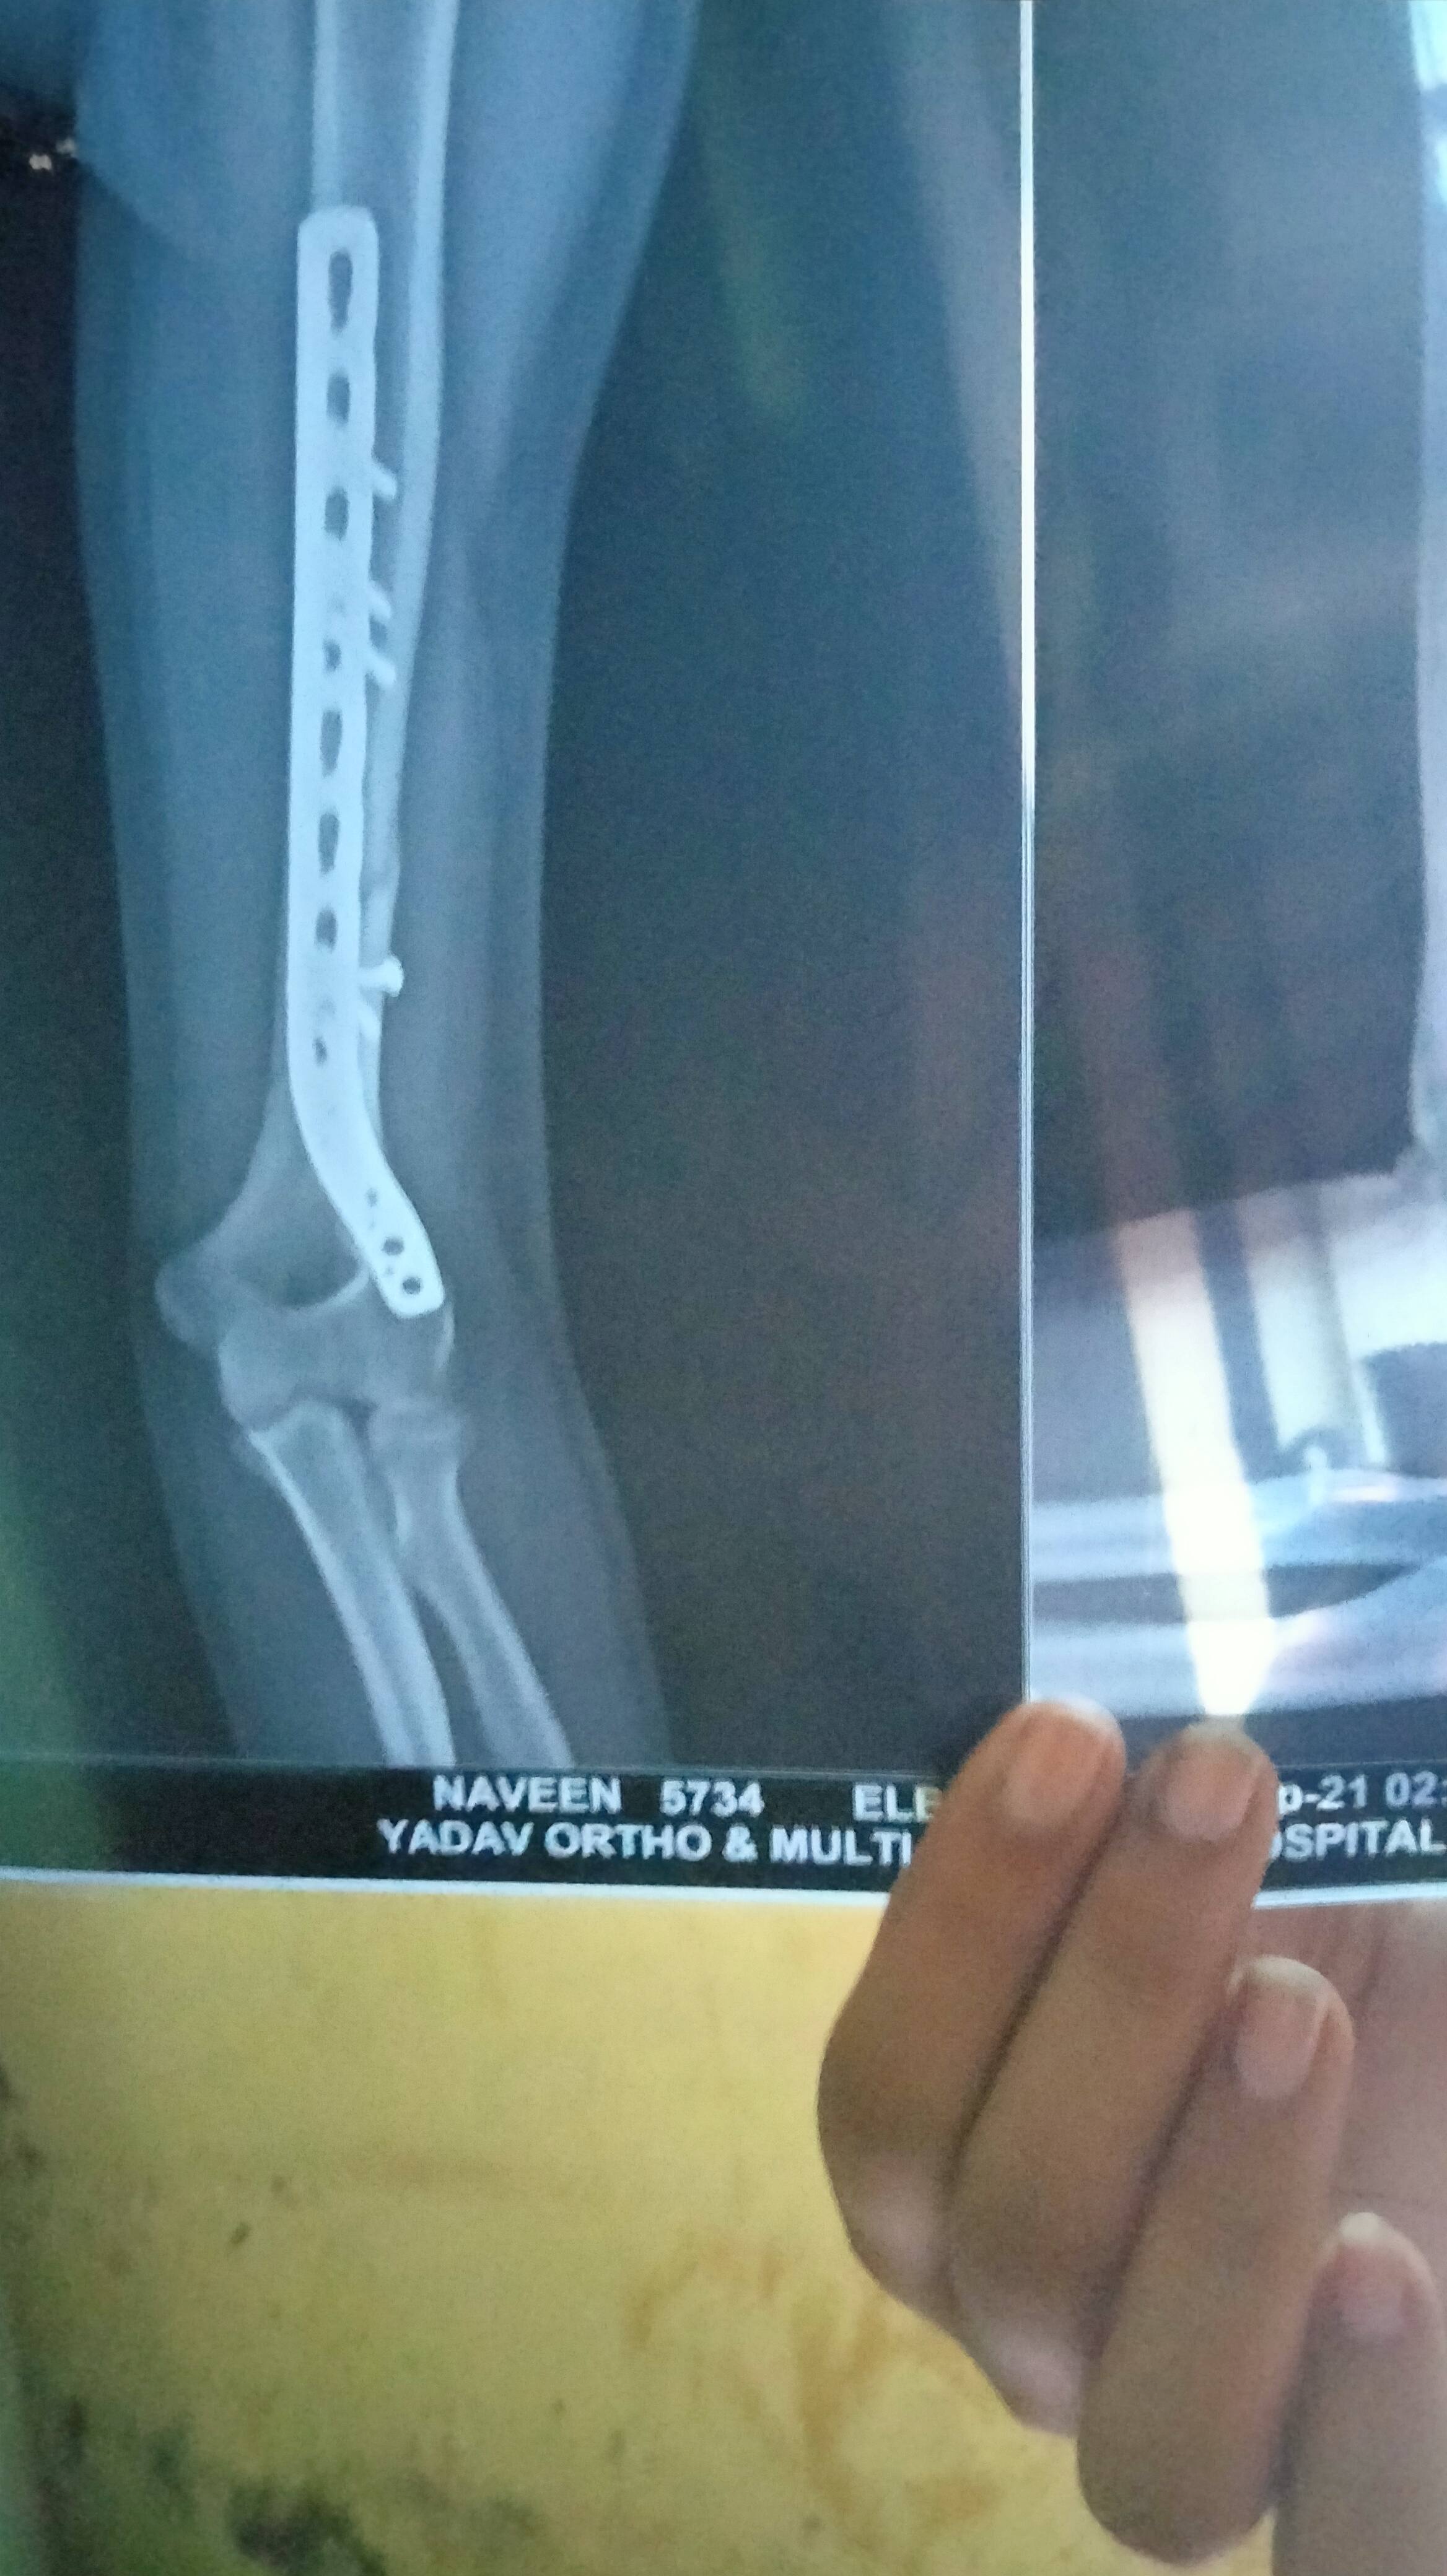

Naveen